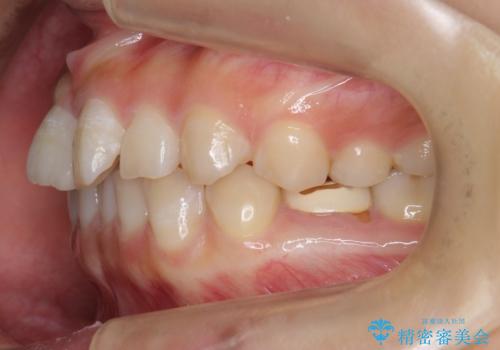

左下に乳歯が残っていましたが、被せ物に穴が空いている状態でした。

乳歯は抜かずに保存的な治療を行いました。

上下の正中が1本分ずれていましたが、ちょうど1本分で目立たず、また、右下の歯が生まれつき少ないことを利用して、最小限の歯の移動にとどめました。

乳歯はまだぐらついたりしていない状態だったため、しっかり虫歯を取り、根の治療も行いました。